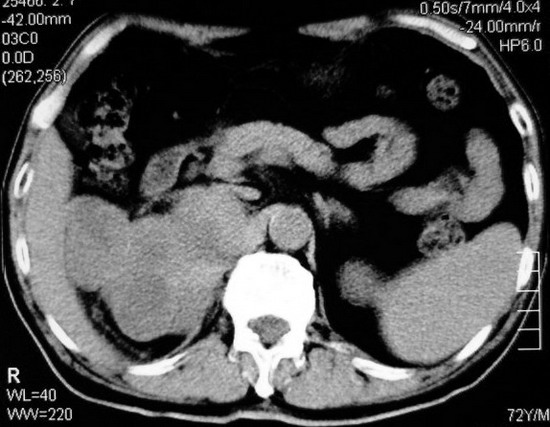

以下是引用杀毒软件在2008-11-17 19:15:00的发言:[br]考虑------右肾癌合并肾静脉---同侧肾上腺受侵可能性大

以下是引用zjzjr在2008-11-17 20:45:00的发言:[br]考虑------右肾癌合并肾静脉---同侧肾上腺受侵可能性大及腹膜后淋巴结转移.